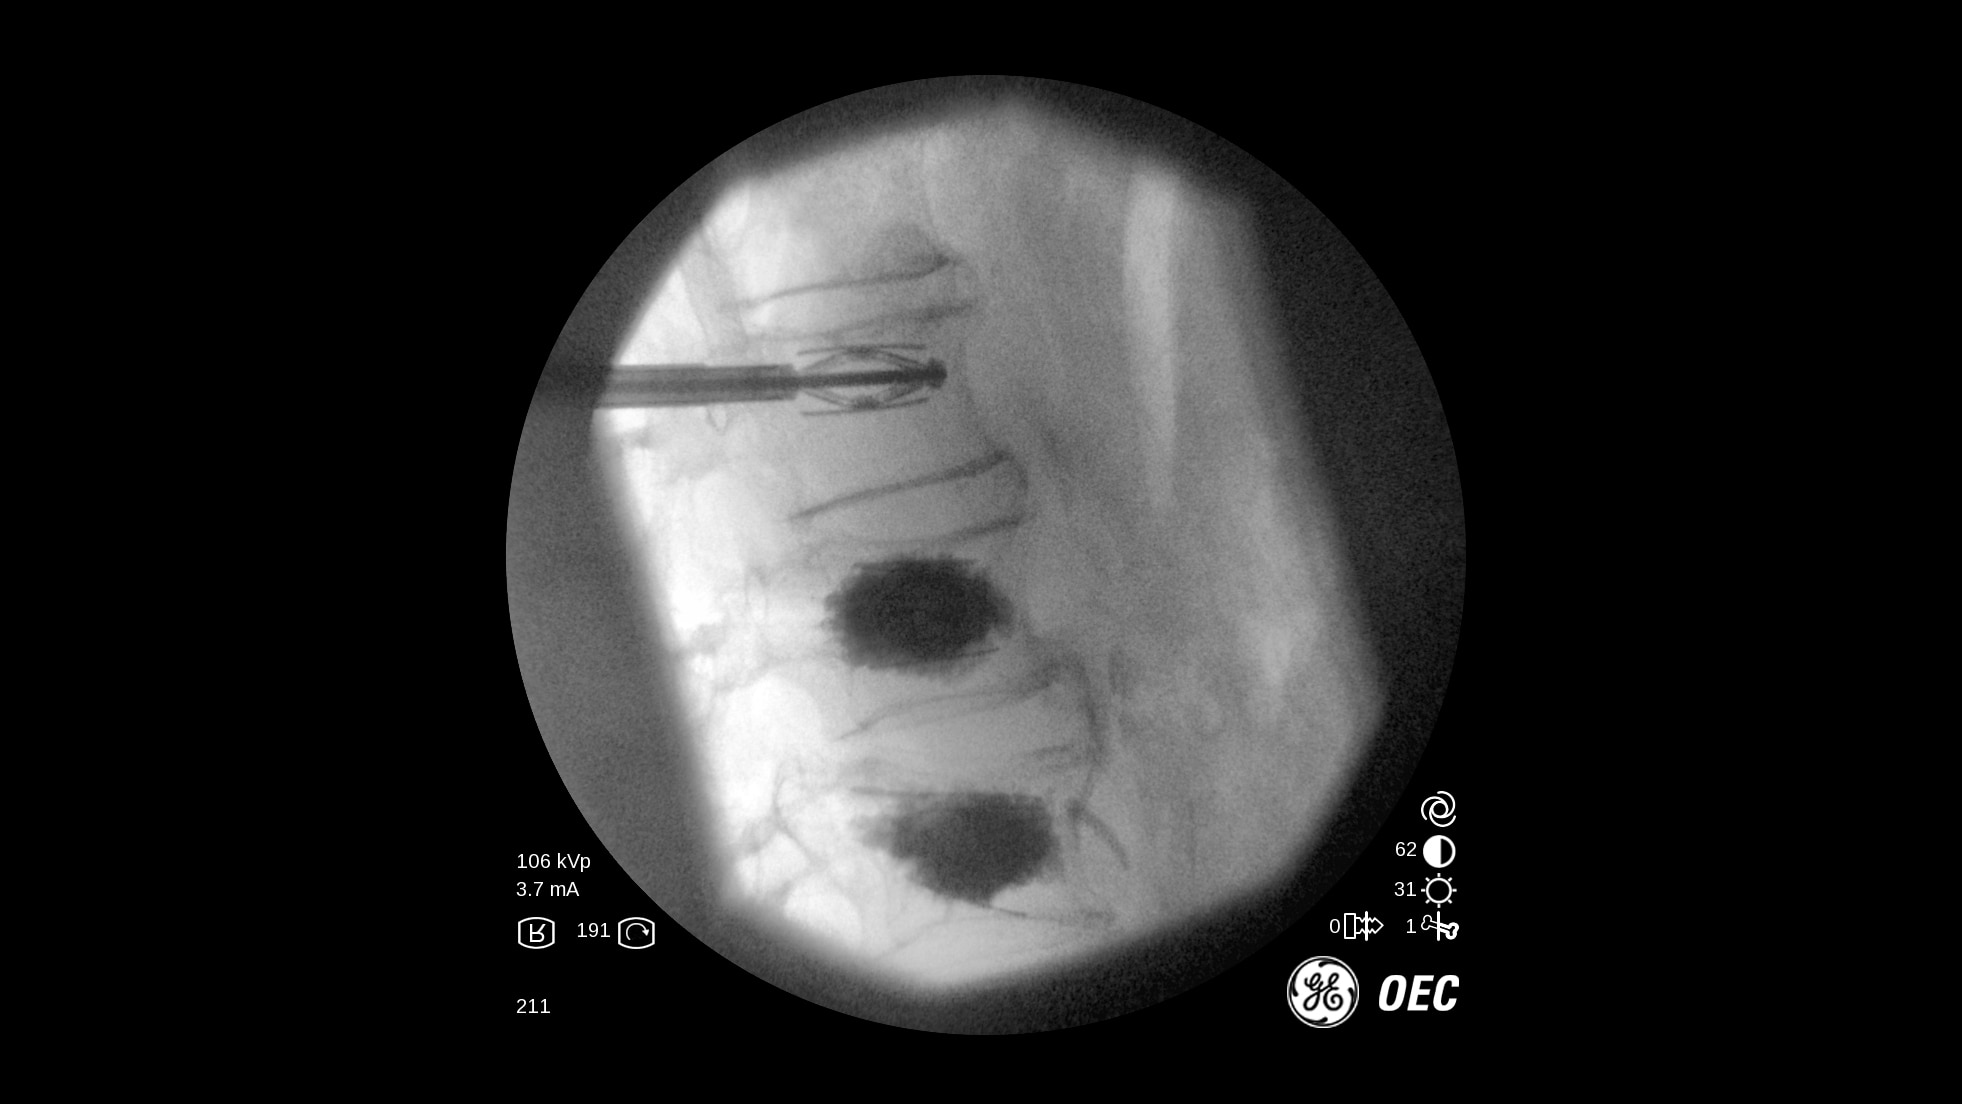

The OEC One all-in-one mobile C-arm offers superb imaging capabilities, made more accessible for a variety of procedures — from pain management to peripheral vascular. Enjoy image processing advancements in clear, detailed images.

Get the images you need without adjusting system settings from the first shot to the last shot with OEC image processing software.

OEC One utilizes automatic intelligence software to sense anatomy and provide high quality imaging at optimal mA and kV levels, even when anatomy is not properly centered in the field of view.